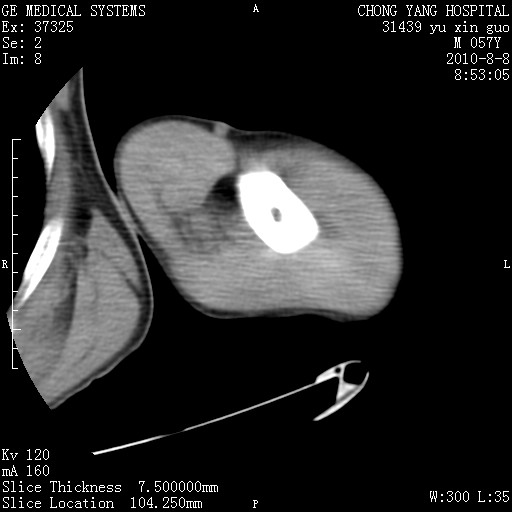

标题: CT28267:M57Y 上臂包块8年余。 [打印本页]

标题: CT28267:M57Y 上臂包块8年余。

上臂软组织内脂肪瘤。

软组织内脂肪瘤

包膜光滑、完整的脂肪密度肿块,支持脂肪瘤。